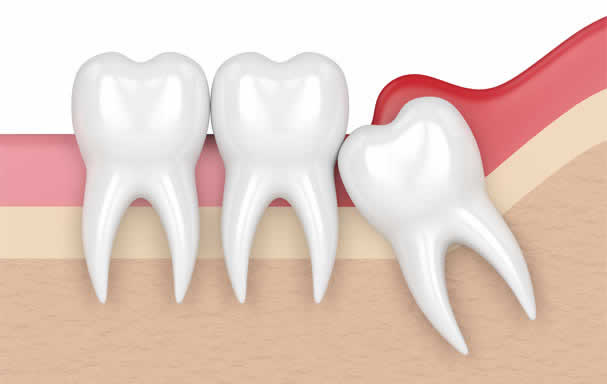

Impacted teeth

Impacted teeth are those that have remained below the gum line or under bone and have failed to erupt. Impacted teeth may also include the third molars, canines, and premolars. When it is determined that they cannot be corrected with orthodontics (braces), they should also be extracted by maxillofacial surgeons through surgery.

Wisdom teeth, also known as third molars, typically emerge between the ages of 17 and 26. While they can remain in the mouth without causing any issues, in some cases, they may need to be extracted. Poor oral hygiene can cause decay, resulting in pain and bad breath. Additionally, limited space in the jaw can cause wisdom teeth to become embedded, which can lead to infections, crooked teeth, and decay of adjacent teeth.

If a wisdom tooth that is embedded or has emerged is causing damage to the adjacent teeth and the surrounding bone due to its position, is located in a position that cannot be cleaned, or has been damaged due to decay or breakage and cannot be treated with filling, root canal treatment, crown, or other treatment methods, it must be extracted.